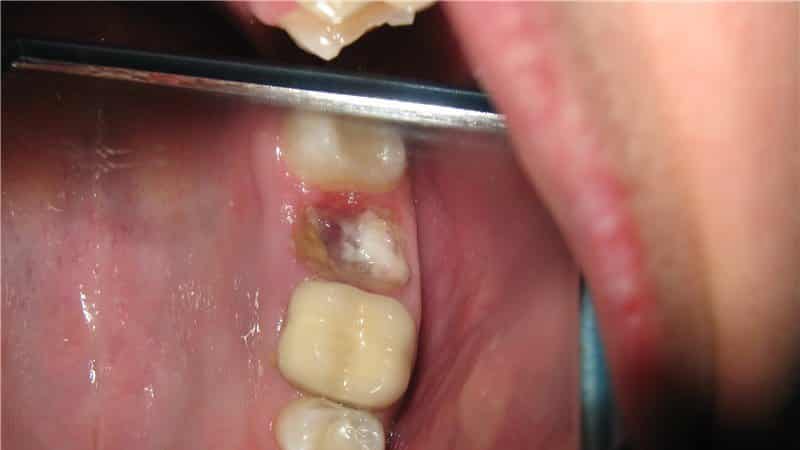

- в процессе операции зуб сломался на несколько частей, которые врач удалял по частям;

Осложнения после операции по удалению зуба развиваются достаточно быстро. Первые клинические симптомы становятся заметными уже к вечеру после операции. Далее мы рассмотрим наиболее распространенные осложнения после удаления зуба.